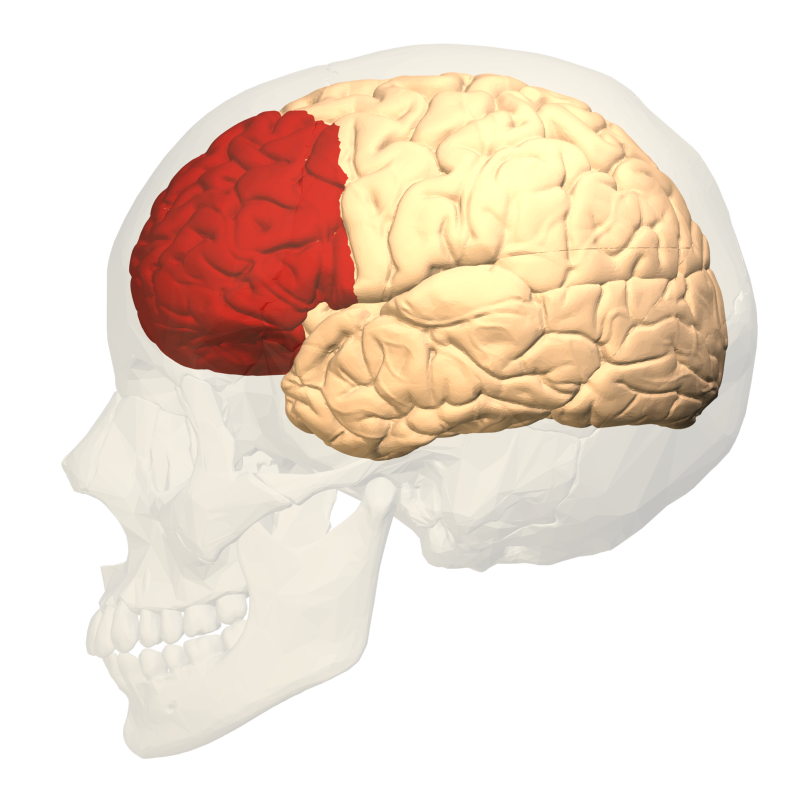

আমাদের মস্তিষ্কের “সেরিব্রাল কর্টেক্স” কতগুলি খণ্ডে বিভক্ত – “ফ্রন্টাল লোব”, “প্যারাইটাল লোব”, “অকিপিটাল লোব”, ও “টেম্পোরাল লোব”।

মস্তিষ্ক সংগৃহীত দৃষ্টি, শব্দ ও ভাষা সম্বন্ধীয় তথ্যগুলিকে স্থানিক উপাংশ ও সময়গত উপাংশে বিশ্লেষণ করার পর দৃষ্টি সম্বন্ধীয় তথ্যের স্থানিক উপাংশগুলি মস্তিষ্কের “ভেন্ট্রাল ইনট্রাপ্যারাইটাল এরিয়া” ও ”ল্যাটারাল ইনট্রাপ্যারাইটাল এরিয়া”-তে এনকোডেড্ (সংকেতাক্ষরে লিখিত) হয় ও তারপর সেরিব্রাল কর্টেক্স এর ফ্রন্টাল লোব এর সামনের দিকে অবস্থিত “প্রিফ্রন্টাল কর্টেক্স” এর কেন্দ্রীয় নির্বাহী অংশটিতে (সেন্ট্রাল এক্সিকিউটিভ পার্ট) আসে। আবার শব্দ ও ভাষা সম্বন্ধীয় তথ্যের স্থানিক উপাংশগুলি “প্রাইমারী অডিটারি কর্টেক্স” এবং “কডাল অডিটারি বেল্ট ও প্যারাবেল্ট”-এ এনকোডেড্ হয়ে প্রিফ্রন্টাল কর্টেক্স এর ঐ একই অংশে আসে। প্রিফ্রন্টাল কর্টেক্স এর কেন্দ্রীয় নির্বাহী অংশটি এই সকল দৃষ্টি, শব্দ ও ভাষা সম্বন্ধীয় এনকোডেড্ তথ্যকে সার্চ ক্রাইটেরিয়া হিসাবে ব্যবহার করে “ডিক্ল্যারেটিভ লং টার্ম মেমোরি” (ব্যক্ত দীর্ঘ মেয়াদী স্মৃতি)-তে এনকোডেড্ অবস্থায় সঞ্চিত বিভিন্ন অভিজ্ঞতা (এক্সপিরিয়েন্স) বা ঘটনা (ইভেন্ট) বা সত্য (ফ্যাক্ট) বা ধারণা (কনসেপ্ট) সম্বন্ধীয় তথ্যগুলির মধ্য থেকে কিছু তথ্য উদ্ধার (রিট্রিভ) করে তাদেরকে ডিকোড্ (পাঠোদ্ধার করা) করে – এই প্রক্রিয়াকেই মস্তিষ্কের “স্মরণ করা” বলা হয়ে থাকে। আর উদ্ধার করা এনকোডেড্ তথ্যগুলিকে ডিকোড্ করার পর তাদেরকে “প্রিফ্রন্টাল কর্টেক্স” এর কেন্দ্রীয় নির্বাহী অংশটি যদি পুনরায় এনক্রিপ্ট করে, সেই প্রক্রিয়ার নামই “যুক্তির ভিত্তিতে নতুন কিছু ভাবা বা চিন্তা করা”[অর্থাৎ একটি মস্তিষ্কের যে কোন নতুন ভাবনা হলো আদতে ঐ মস্তিষ্কেরই কোন না কোন স্মৃতির এনক্রিপ্টেড্ রূপ]।